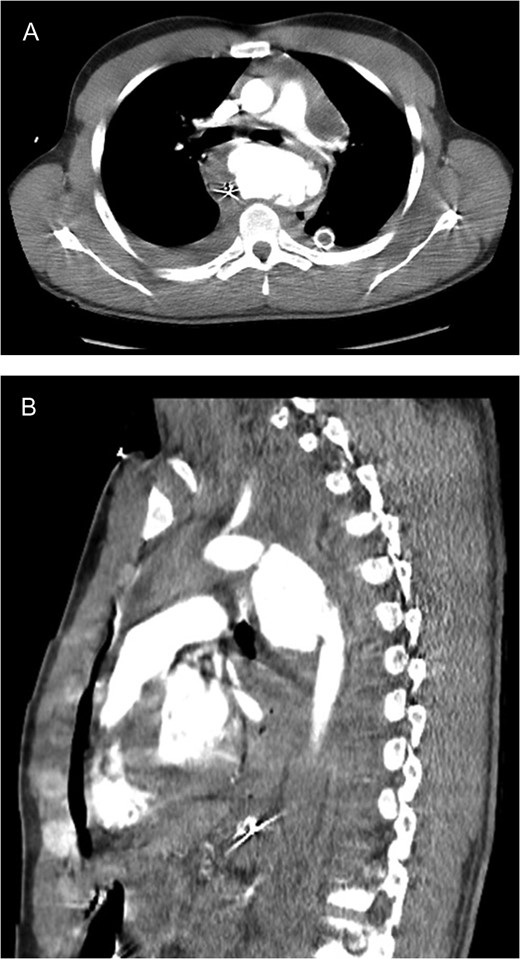

CT scan images (A axial; B sagittal) demonstrating aortic rupture with active contrast extravasation at the level of the proximal descending aorta just distal to the ductus on both axial and sagittal imaging.

Bilateral femoral arteries were accessed and an aortic endovascular stent was deployed to cover the area of injury. During the procedure, the patient developed significant hemorrhage from the left chest and became hypotensive. An emergent left thoracotomy was performed and the mediastinum was packed temporarily while the vascular team deployed an additional two stents over the area of injury, including the origin of the left subclavian artery. This resulted in exclusion of the aortic injury with no signs of radiographic leak.